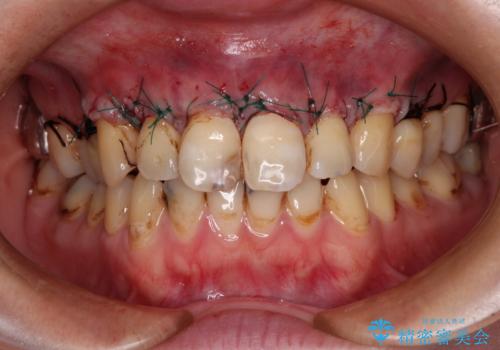

前歯は着色や虫歯治療の跡が目立っている状態で、オールセラミッククラウンによる審美治療を希望されていました。

歯肉が非常に菲薄であり、オールセラミッククラウンを装着後の近い将来歯肉退縮によりセラミックの境目が見えてくることが懸念されました。

まずは歯肉移植術により顕著に露出している歯根面を被覆して自然な歯肉ラインとし、同時に歯肉の厚みを増大させることで将来の歯肉退縮を予防することを提案しました。